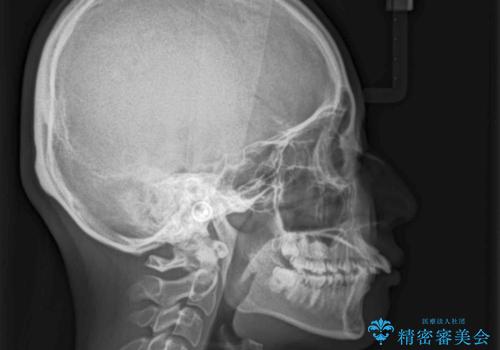

飛び出した前歯を引っ込めたい 目立たないワイヤーでの抜歯矯正

- 口元の閉じにくさと、前歯のでこぼこの歯並びを気にして来院された患者様です。

口元を積極的に引っ込めるために、上下左右の小臼歯計4本を抜歯することとしました。

咬み合わせが深く、咬合力強いため、補助装置を使用しながら積極的に口元を下げることとしました。